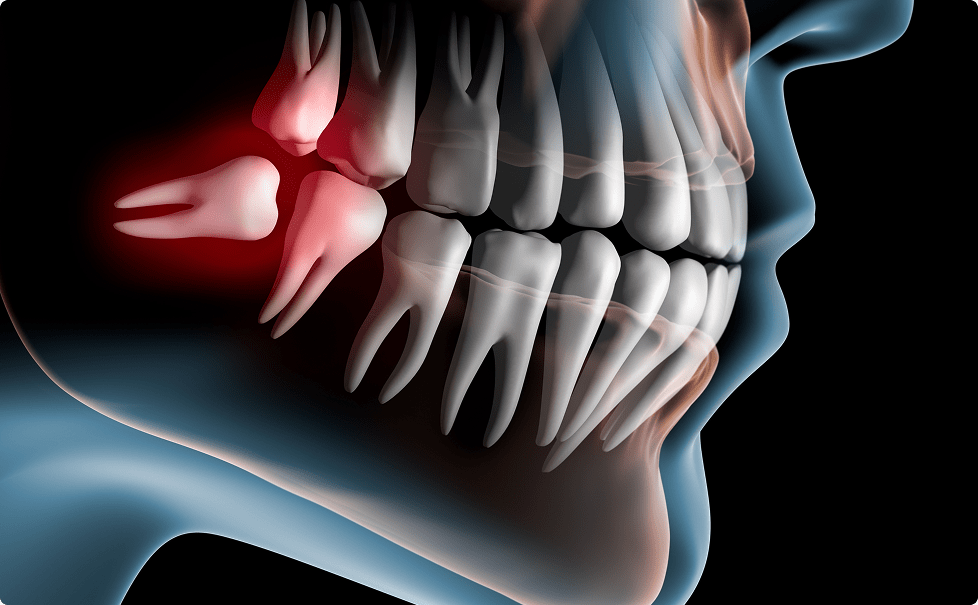

智歯周囲炎

親知らず周囲に汚れがついて歯茎が腫れてしまいます。症状が強く出れば、お口が開けづらくなり、熱が出ることもあります。顔の形が変わるくらい腫れることもよくあります。飲み薬で効きにくい場合は紹介させていただいて点滴処置も必要になることもあります。

歯周病、むし歯

歯周囲炎と関連しますが、慢性的(定期的にずっと)に汚れが停滞していると、手前の歯にむし歯を作ったり歯周病を憎悪してしまう可能性があり、親知らずを抜歯したとしても手前の歯も大きくダメージを負う場合もあり、最悪の場合手前の歯の抜歯の可能性もあります。